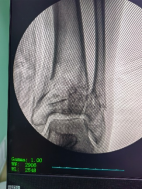

透視檢查骨折端

控制機器人牽引斷端,可見關(guān)節(jié)間隙恢復。